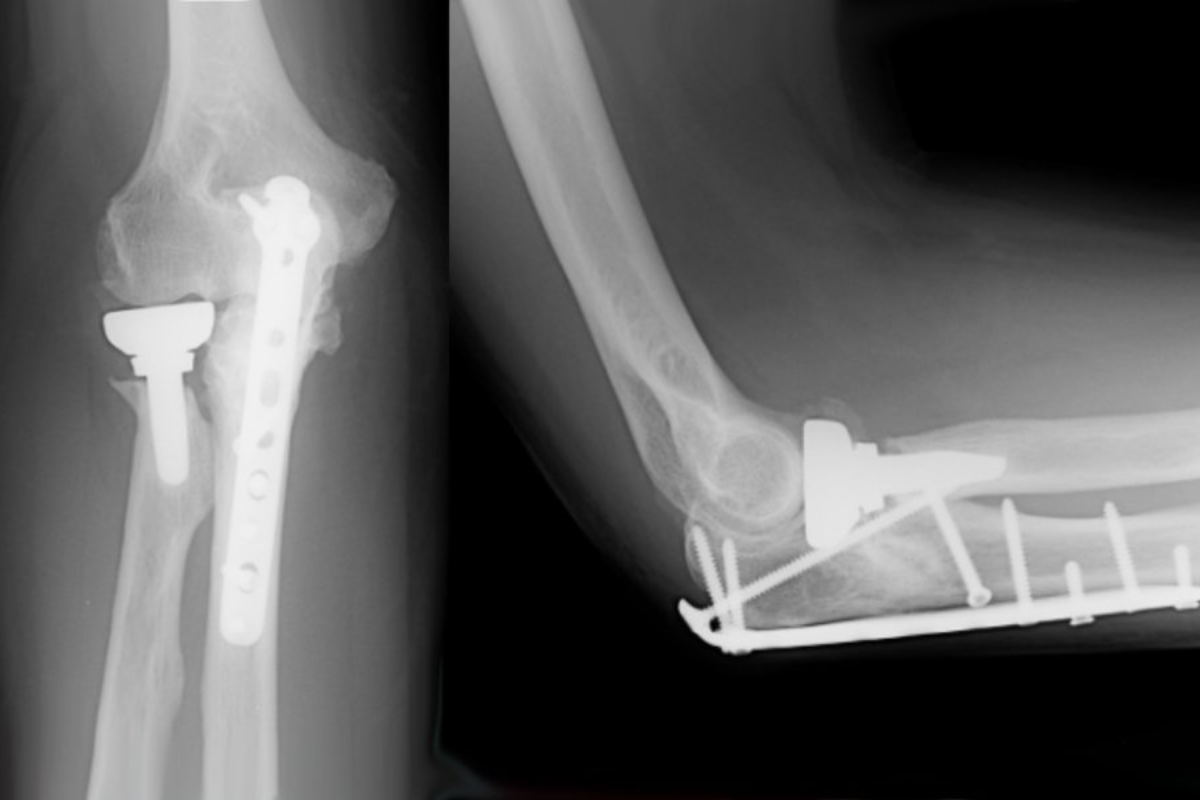

Since its founding Bobade Hospital has been providing its patients with the full medical care, encompassing outpatients services, is neurology, laboratory, imaging diagnostics and more.